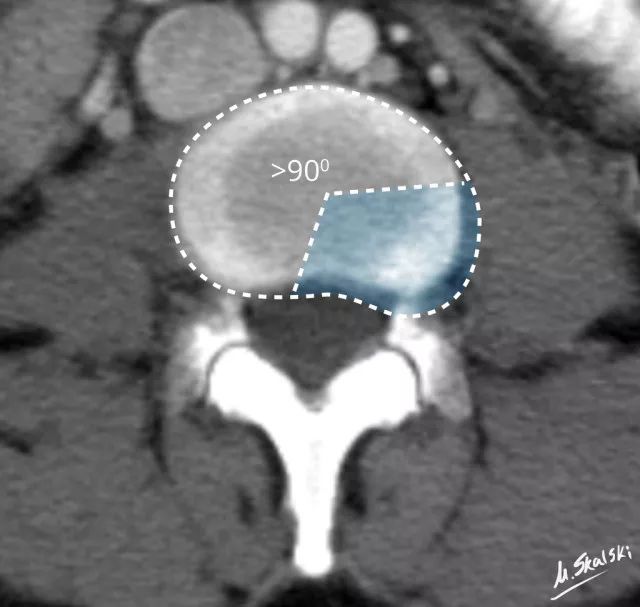

椎间盘膨出(Disc bulge)

纤维环松弛但完整 , 髓核皱缩 , 表现为纤维环均匀超出椎体终板边缘 。

椎间盘膨出的影像学定义为突出部分>椎间盘边缘的25% , 或者突出的两边与髓核的中心的夹角>90°

临床表现

一般无临床症状 , 有时可因椎间隙狭窄 , 椎节不稳 , 关节突继发性改变 , 出现反覆腰痛 , 很少出现根性症状 。 如同时合并发育性椎管狭窄 , 则表现为椎管狭窄症 , 应行椎管减压 。